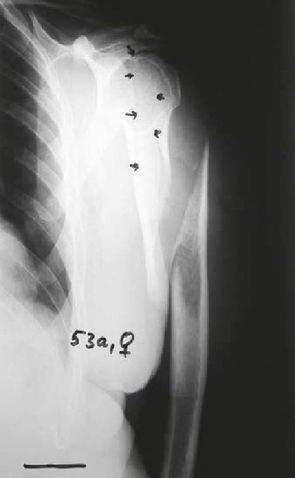

Long spiral fracture A1 with fissure extensions into the head in a 56-year-old woman. First of all rope cerclage via minimal intervention to restore the anatomy as a prerequisite for effective insertion of the BONEHELIX® in the same session. Rapid healing, free function.